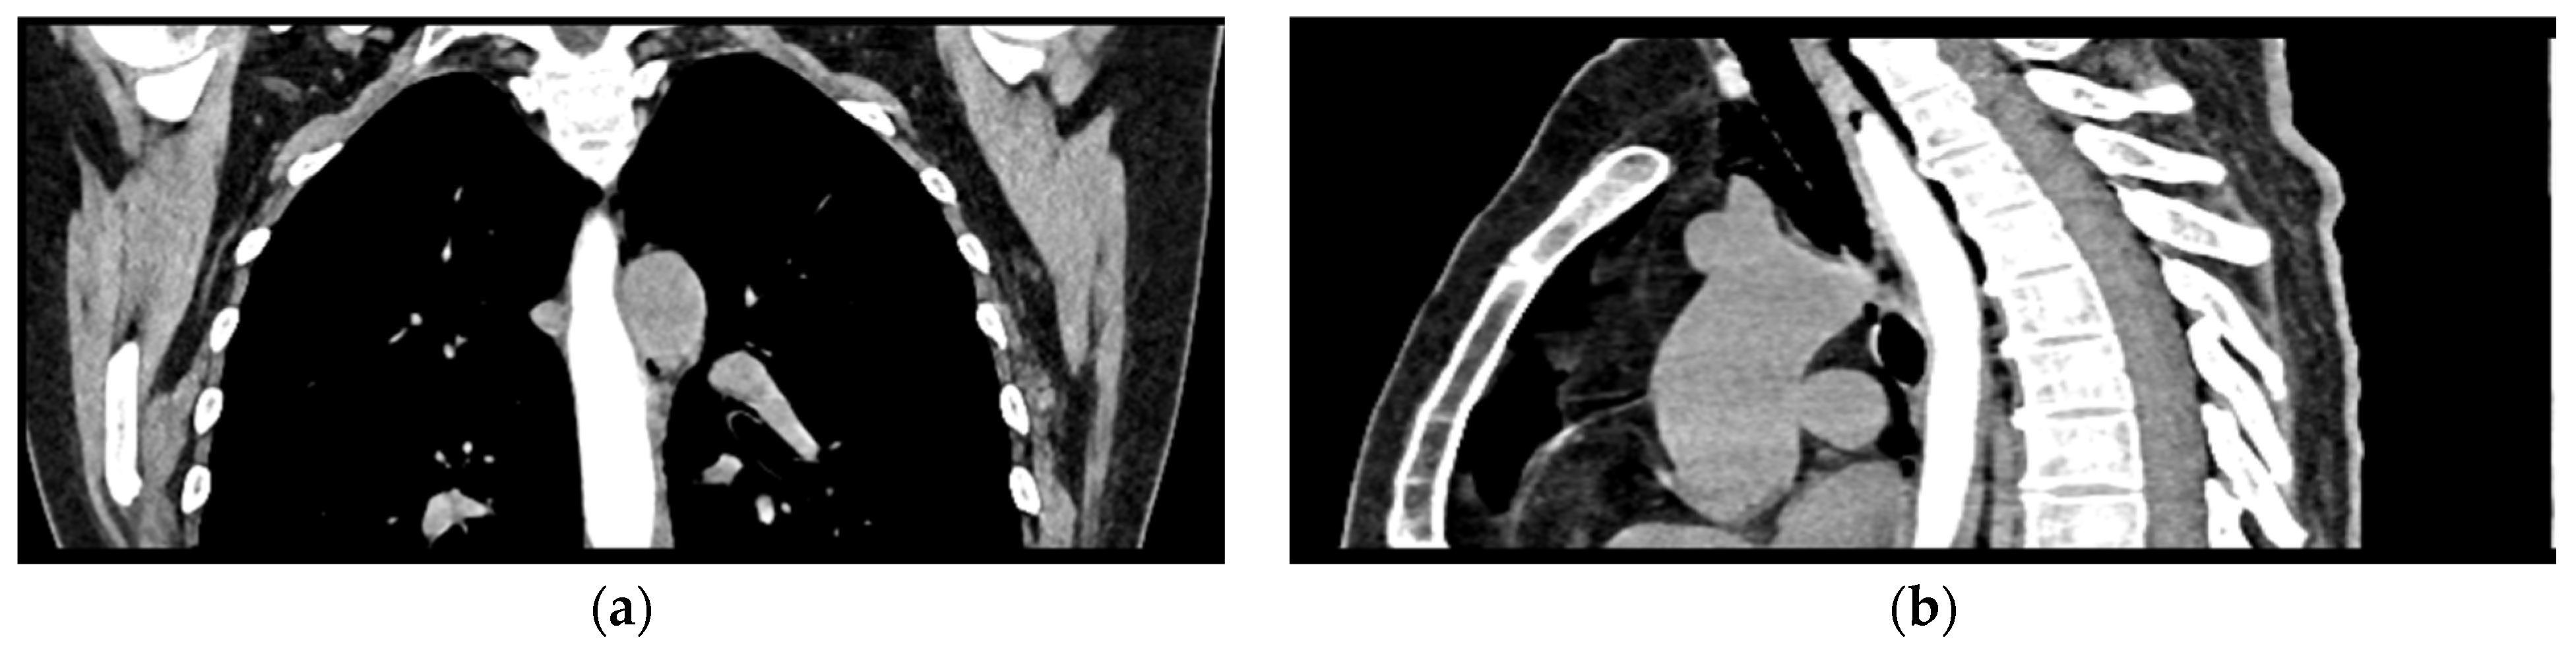

The chest CT scan performed in the emergency department (Figure 1) revealed the presence of pneumomediastinum. CT scans of the abdomen and pelvis were also performed, giving the high lipase and epigastric pain, revealing findings consistent with acute pancreatitis (with peripancreatic fluid collection, consistent with moderate acute pancreatitis per the modified CT severity index), as well as a solitary gallbladder stone measuring approximately 20 mm in diameter, without intra or extrahepatic biliary ducts enlargement (Figure 2).

Figure 1.

Initial chest CT scan, demonstrating pneumomediastinum (arrows): (a) axial view showing free air in the mediastinal space; (b) coronal view revealing air tracking along several mediastinal structures.